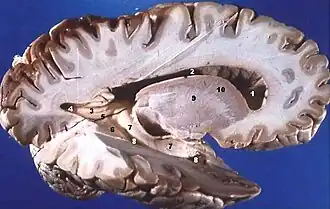

Human brain right dissected lateral view